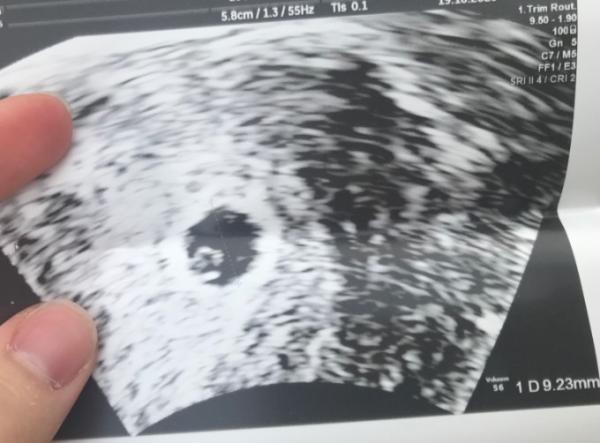

Oh super! Das doch wunderbar Ich war gestern außerplanmäßig kurz beim Arzt, wegen heftigster Bauchweh und obwohl ich nix erwartet habe bei 4+4, habe ich ein kleines Foto erhalten LG

Bild zu